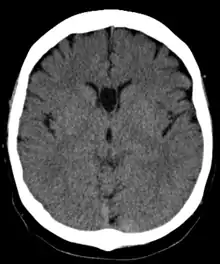

The cave of septum pellucidum (CSP), cavum septi pellucidi, or cavity of septum pellucidum is a slit-like space in the septum pellucidum that is present in fetuses but usually fuses during infancy. The septum pellucidum is a thin, laminated translucent vertical membrane in the midline of the brain separating the anterior horns of the right and left ventricles. It lies posterior to the corpus callosum. Persistence of the cave of septum pellucidum after infancy has been loosely associated with neural maldevelopment and several mental disorders that correlate with decreased brain tissue.[1][2][3][4][5]

The cave of septum pellucidum is bounded anteriorly by the genu of the corpus callosum, superiorly by the body of the corpus callosum, posteriorly by the anterior limb and pillars of the fornix, inferiorly by the anterior commissure and the rostrum of the corpus callosum, and laterally by the leaflets of the septum pellucidum.[6]

There are individual differences in the degree of CSP; whereas some have complete closure of the cavum, others present with a small degree (4–6 mm wide, in the coronal plane) of incomplete closure.[4] The most common type of CSP is noncommunicating; that is, it does not connect to the brain's ventricular system. Because of this lack of communication, the previous use of the term "fifth ventricle" is no longer used, and the fifth ventricle is the name often used for the terminal ventricle.